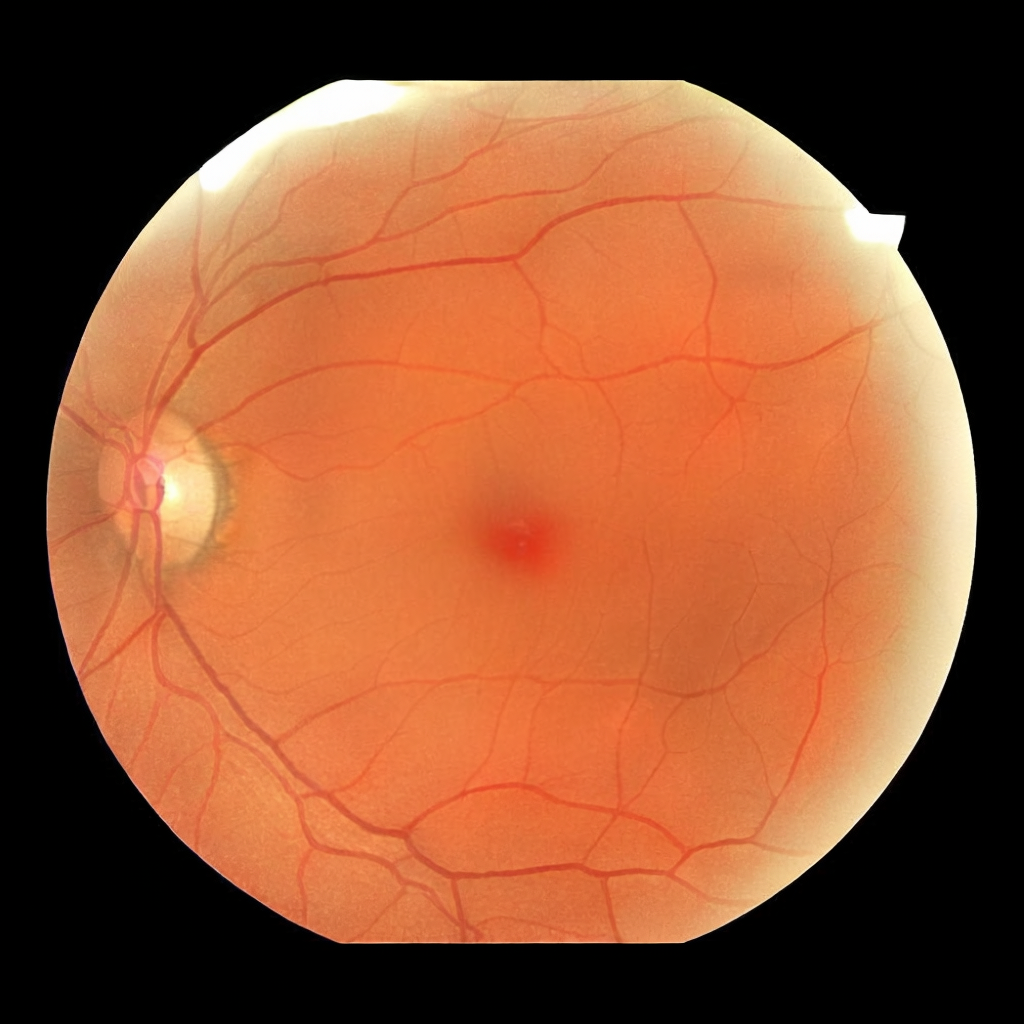

Diffusion models have recently gained significant traction due to their ability to generate high-fidelity and diverse images and videos conditioned on text prompts. In medicine, this application promises to address the critical challenge of data scarcity, a consequence of barriers in data sharing, stringent patient privacy regulations, and disparities in patient population and demographics. By generating realistic and varying medical 2D and 3D images, these models offer a rich, privacy-respecting resource for algorithmic training and research. To this end, we introduce MediSyn, a pair of instruction-tuned text-guided latent diffusion models with the ability to generate high-fidelity and diverse medical 2D and 3D images across specialties and modalities. Through established metrics, we show significant improvement in broad medical image and video synthesis guided by text prompts.

In this work, we focus on the ability of LDMs to generate novel datasets to overcome class imbalances traditionally associated with medical data, and potentially reduce the need for manual annotation of medical 2D and 3D data. We present MediSyn, a pair of text-guided latent diffusion models for broad medical 2D and 3D modality synthesis. To overcome the scarcity of labelled medical data, we leverage a vast corpus of more than 5 million image-caption pairs and 100,000 video-caption pairs collected from the public domain across numerous medical specialties, and integrate comprehensive natural language annotations to develop a pair of versatile diffusion models for the medical domain.

We assembled a set of 5,785,333 medical image-caption pairs, covering 8 specialties and 9 imaging modalities, to train Medisyn’s 2D model. We reserved an additional 1000 image-caption pairs (125 pairs from each specialty) for model evaluation.

| Ophthalmology | 174,246 |

| Light Photography | 174,246 |

Our findings demonstrate Medisyn’s remarkable ability to generate high-fidelity and diverse medical images, image sequences and volumetric scans across various medical subspecialties and imaging modalities. Other medical text-driven diffusion models, such as TauPETGen [42] for tau PET images and GenerateCT [43] for chest CT volumes, have proven successful in generating high-quality images that accurately depict anatomical features and clinical conditions. However, these models are constrained to a single imaging modality and anatomical region, thereby restricting their applicability. Moreover, they were trained on relatively small datasets sourced from a limited number of institutions, which could lead to more biased outputs. In contrast, Medisyn, having been trained on one of the largest publicly accessible medical image and video datasets to date, is equipped to synthesize data that cover numerous medical disciplines, population groups, and disease states. Leveraging our two models, we can synthesize new medical datasets as well as augment existing ones, potentially improving a wide array of medical machine learning tools, both general and specialized. Additionally, our models can minimize the need to repeatedly fine-tune on specific datasets for generating different imaging modalities, thus reducing computational costs for academic labs.

In summary, we introduced a pair of text-conditional LDMs trained on an extensive medical image and video dataset covering various medical subspecialties and imaging modalities. By generating high-fidelity and diverse medical 2D and 3D images, Medisyn illustrates the potential for a singular framework to broadly address the challenge of data scarcity in healthcare.